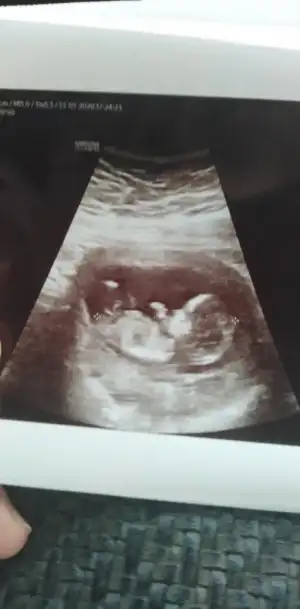

Teyzeleri bize bakabilir misiniz acaba cinsiyet ne ola ki 11. Haftaya gireceğiz 😍